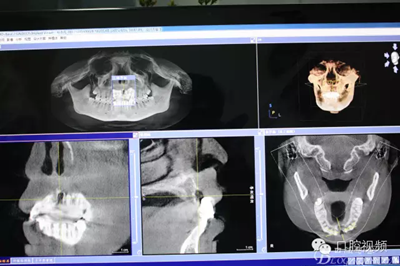

【原創(chuàng)博客】烤瓷橋下的悲劇-張東星